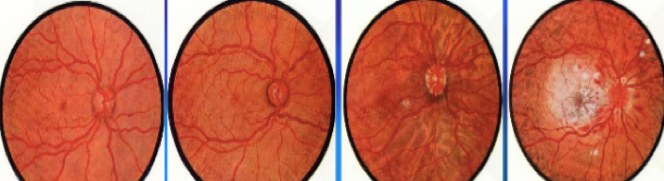

(1)细动脉硬化 细动脉硬化表现为细动脉玻璃样变,是缓进型高血压的基本病变。发生于全身各器官的细动脉(直径<1 mm的、中膜仅有1~2层SMC的最小动脉,如视网膜动脉、脾小体中央动脉、肾小球入球动脉﹚。 由于细动脉反复痉挛,内皮细胞和基底膜受损,内皮细胞间隙扩大,内膜通透性升高,血浆蛋白注入内皮下间隙;同时内皮细胞及中膜SMC分泌ECM增多,继而SMC凋亡,导致管壁发生玻璃样变性。

光镜下,细动脉管壁呈均质红染,管壁增厚,管腔变小。心电图显示左心室轻度肥大。 |

(4)视网膜